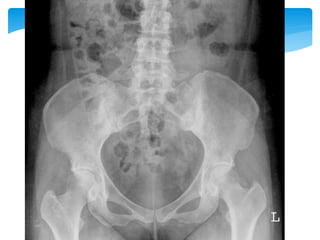

2~5年 Modified New York criteria 1984

1. 下背痛僵硬 休息無法減輕 三個月以上

2. 腰椎活動範圍受限

3. 擴胸範圍受限

4. X光有薦腸關節炎雙側2級或單側3級以上 4+ 1

or 2 or3